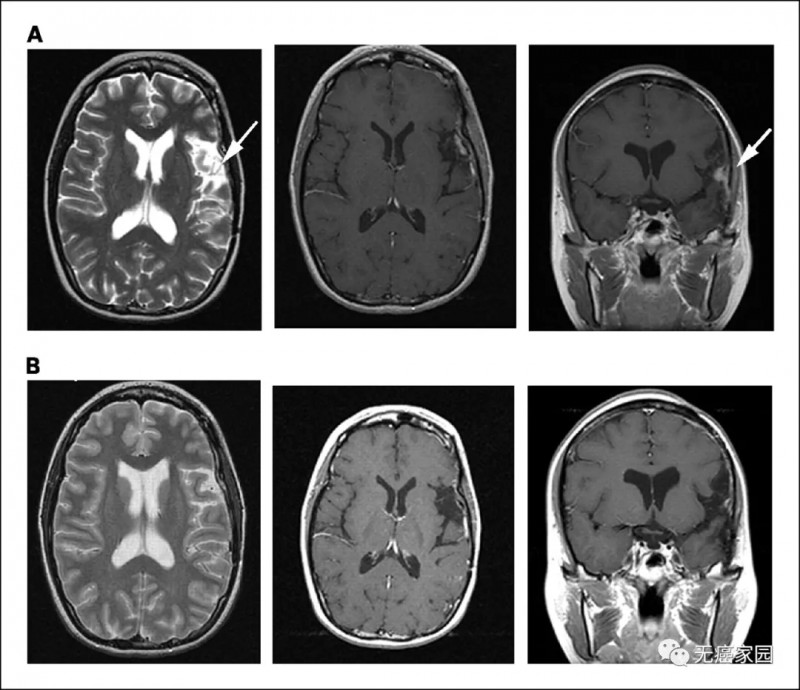

其中有一名患者在完成肽脉冲树突状细胞疫苗接种后2个月且进行任何其他辅助治疗之后,磁共振成像(MRI)显示残留的肿瘤几乎完全消退。有趣的是,经过近5年的随访,她目前还活着,没有临床或MRI证据表明肿瘤复发。

患者5的脑部MRI扫描图

A:在树突状细胞注射之前

B:完成肽脉冲树突状细胞疫苗系列的2个月后

(箭头所指区域在树突状细胞疫苗治疗后消失)